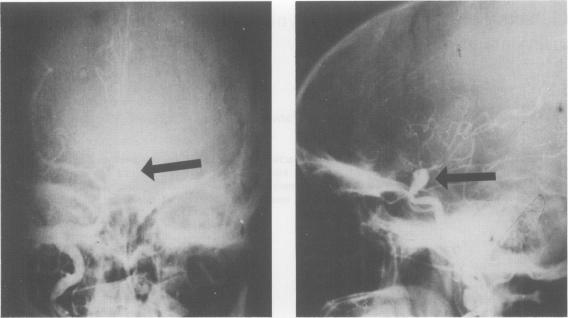

A 32 year old female with hyperprolactinaemia-galactorrhoea-amenorrhoea due to a right internal carotid artery aneurysm just before its bifurcation is described. She had two episodes of subarachnoid haemorrhage necessitating an emergency internal carotid artery ligation. She responded to bromocriptine treatment with restoration of her menses, normalization of circulating prolactin and disappearance of galactorrhoea.

本文描述了一名32岁女性,因右侧颈内动脉动脉瘤(恰好在其分叉前)导致高泌乳素血症 - 溢乳 - 闭经。她曾发生过两次蛛网膜下腔出血,需要紧急进行颈内动脉结扎术。她对溴隐亭治疗有反应,月经恢复,循环泌乳素水平正常,溢乳消失。